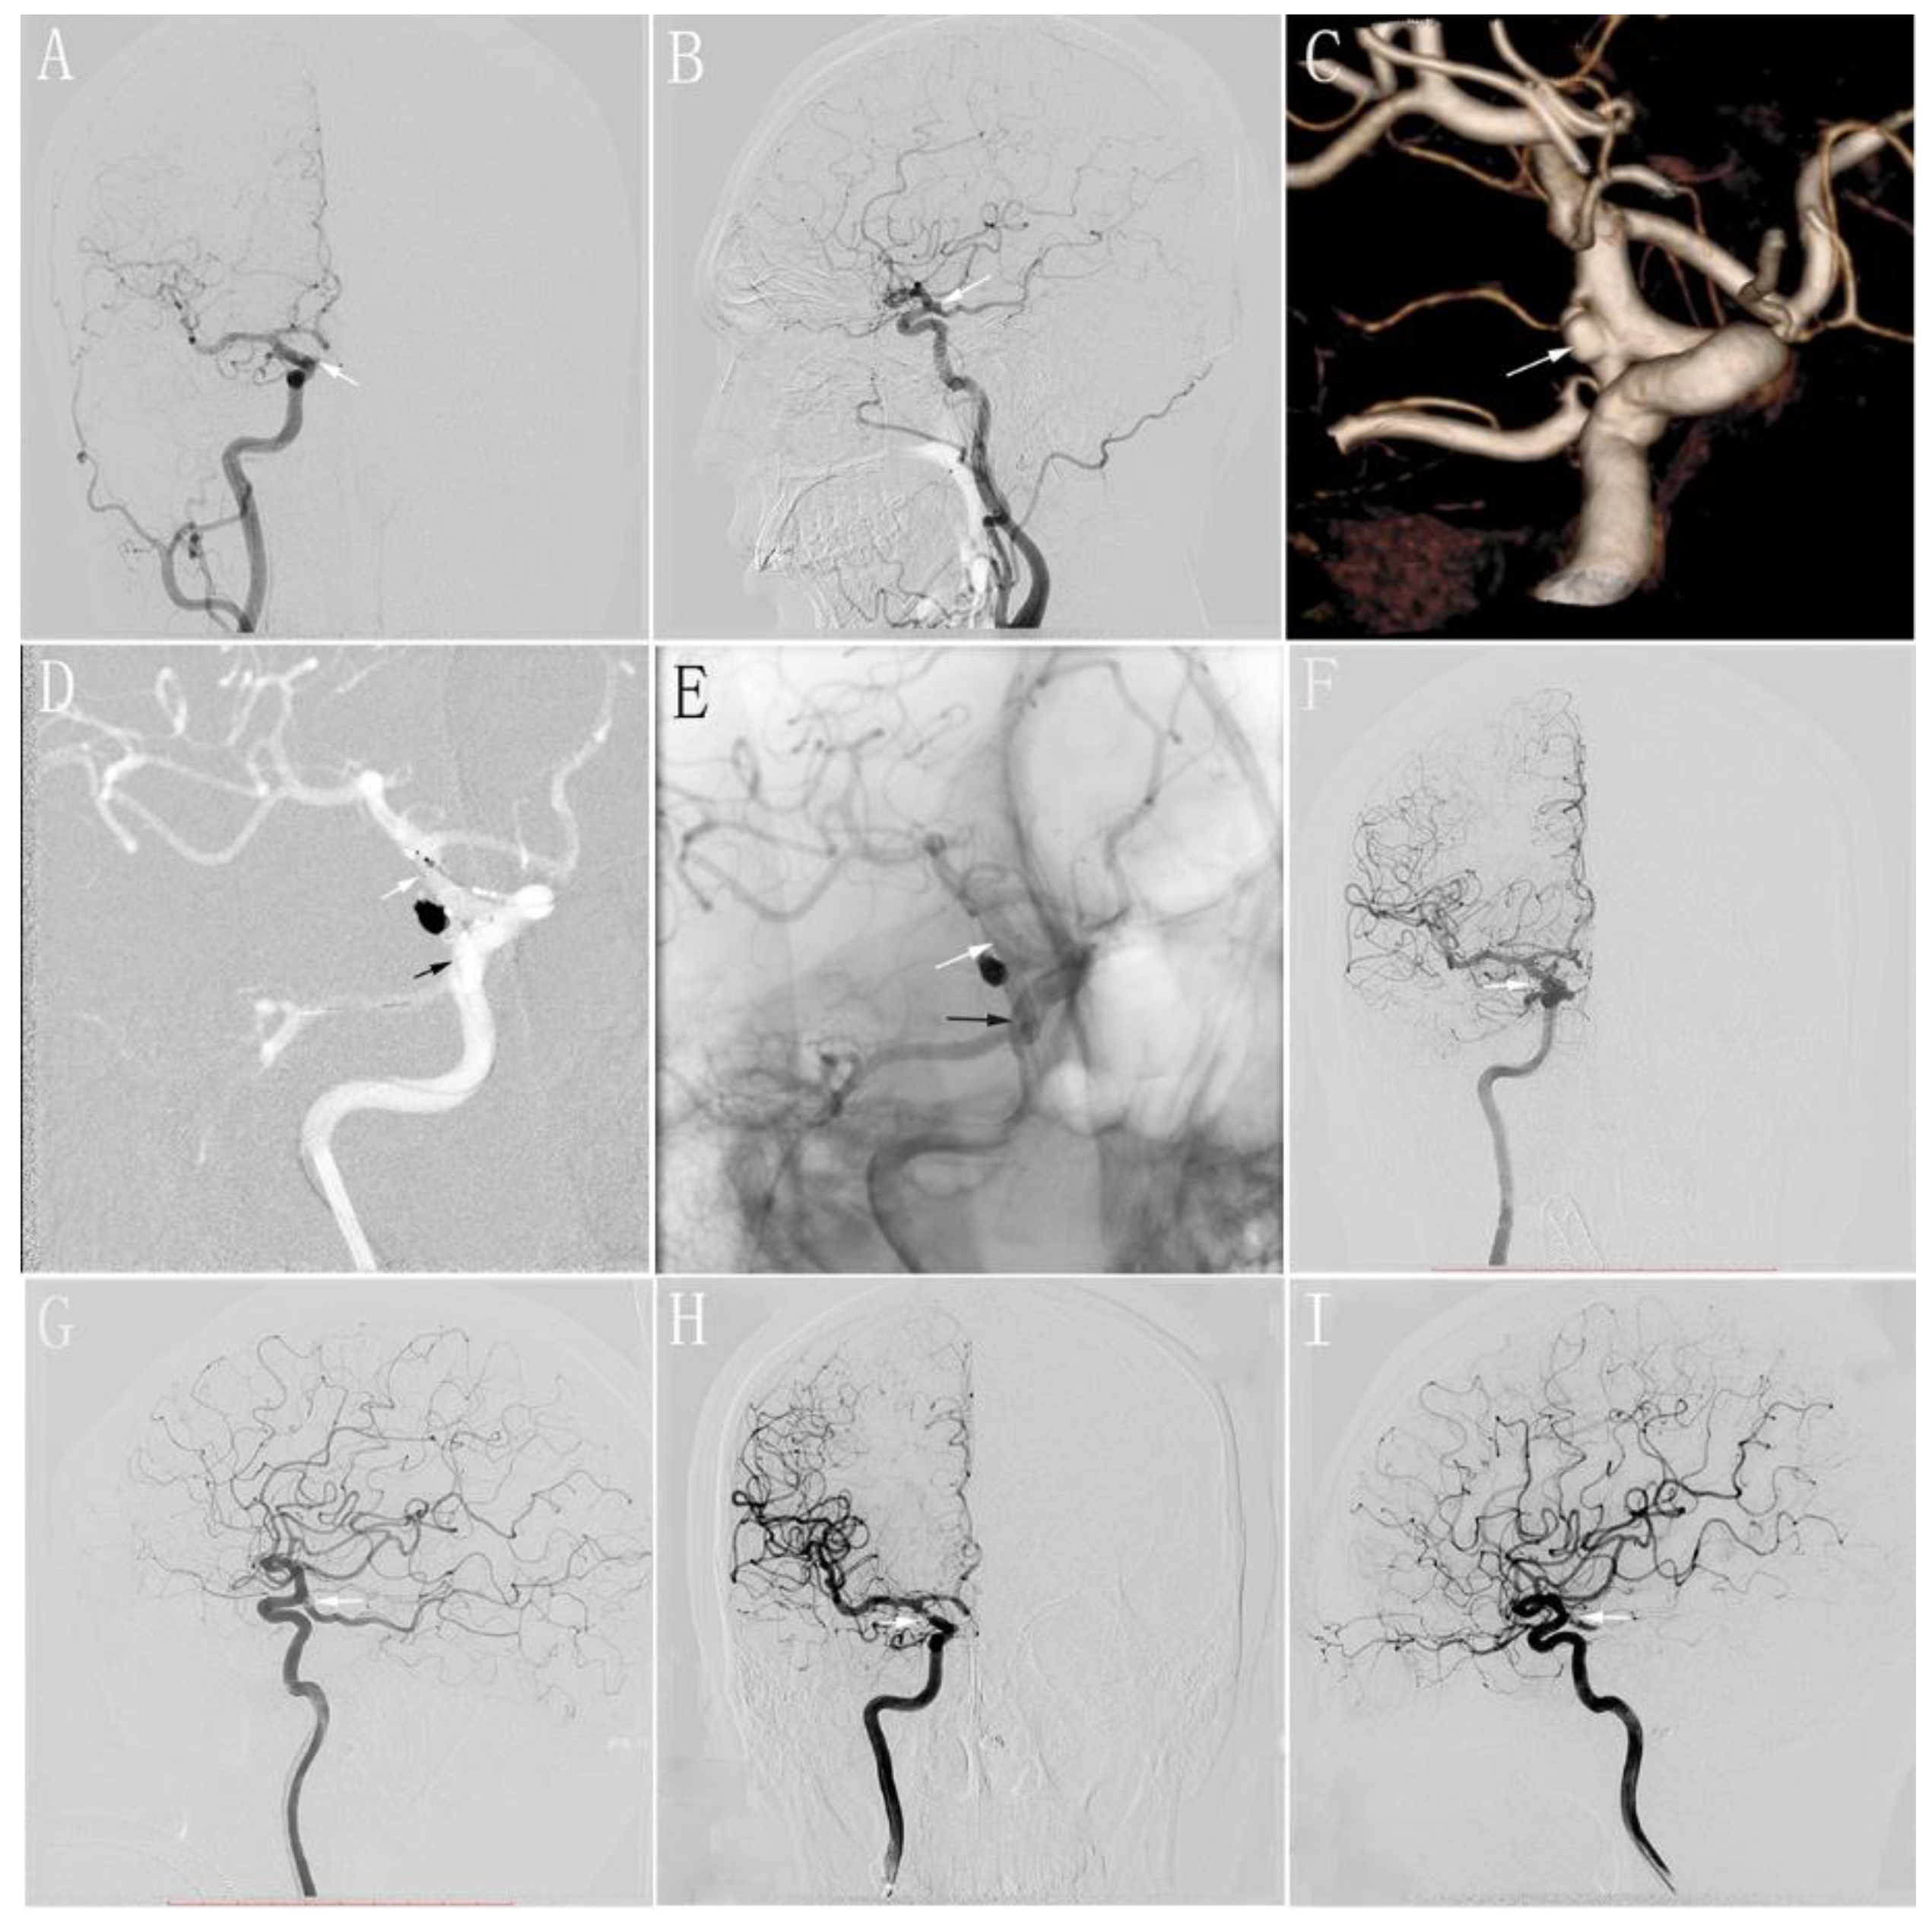

In this study, all patients tolerated the procedure well, without any intraprocedural complications. Nine patients with nine aneurysms underwent endovascular treatment (SACs) using the swinging-tail technique by Prof. Lv. Additionally, all patients successfully underwent SACs using the swinging-tail technique (Figure 3). To reduce the recurrence rate of aneurysms, we aimed to achieve complete occlusion of the aneurysmal sac, with the assistance of the stent. All patients achieved complete occlusion of the aneurysm, as shown by an immediate postoperative angiography.

Figure 3. (A,B): Preoperative anteroposterior (A) and lateral (B) DSA of the R-ICA showing a wide-necked aneurysm that is located in the origin of the PCoA (white arrow); (C): Preoperative three-dimensional reconstruction of the R-ICA showing a wide-necked aneurysm (white arrow); (D): The stent is completely released by the swinging-tail technique. The distal segment of the stent is located in the PCoA (black arrow) and the proximal segment of the stent is located in the distal segment of the R-ICA at the ostium of the PCoA (white arrow); (E): Postoperative immediate unsubtracted DSA showing the location of stent (black arrow: the distal segment of the stent; white arrow: the proximal segment of the stent); (F,G): Postoperative immediate anteroposterior (F) and lateral (G) DSA of the R-ICA showing complete occlusion of the aneurysm (white arrow); (H,I): Anteroposterior (F) and lateral (G) DSA at 6 months of follow-up postoperatively of the R-ICA showing complete occlusion of the aneurysm (white arrow). DSA: digital subtraction angiography; PCoA: posterior communicating artery; ICA: internal carotid artery.